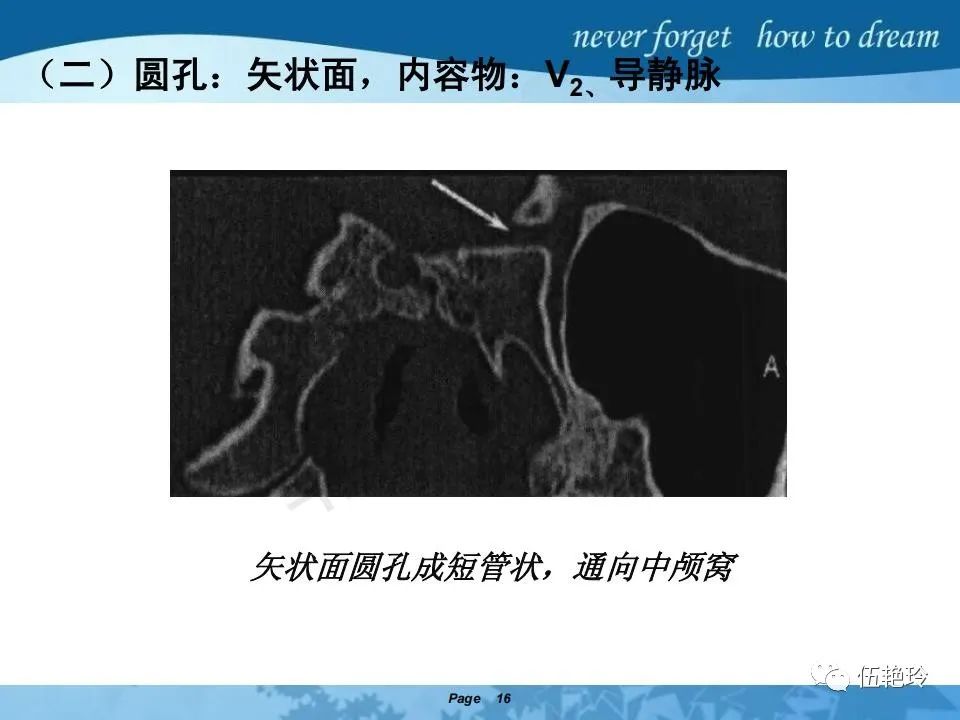

翼腭窝的解剖结构与鼻咽癌侵犯

2.31 向上颅内:①鼻咽顶壁→破裂孔(岩尖、斜坡)→蝶窦、海绵窦;②鼻咽顶壁→蝶骨基底部→蝶窦、海绵窦;③鼻咽侧壁→茎突前间隙→蝶骨大翼(卵圆孔)→海绵窦;④鼻咽侧壁→茎突前间隙→翼腭窝→ 颞下窝;⑤鼻咽前壁→鼻腔→翼突、翼腭窝→眶下裂→眶尖→海绵窦;⑥鼻咽前壁→鼻腔→上颌窦、筛窦;